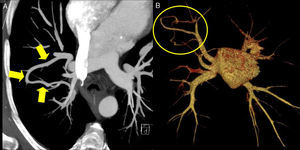

A) TC torácica con reconstrucción de proyección de máxima intensidad (MIP) en la que se identifica una estructura vascular tubular que comunica 2 venas pulmonares. B) TC torácica con reconstrucción de volume rendering (VR) en la que únicamente se visualizan las venas pulmonares y la aurícula izquierda, objetivándose la conexión entre las venas pulmonares derechas correspondiente a la variz venosa pulmonar.

El ecocardiograma transtorácico con contraste no demostró shunt extracardíaco derecha-izquierda, siendo el restante examen ecocardiográfico, la gasometría y la espirometría normales. La angio-TC pulmonar demostró una vena pulmonar hipertrofiada que comunica la vena del segmento anterior con la del segmento posterior del lóbulo superior derecho, sugestiva de variz venosa, drenando a la vena pulmonar superior derecha.

La variz venosa pulmonar es una entidad rara, definida como una dilatación patológica focal de una vena pulmonar, que puede ser aislada o asociarse a hipertensión venosa pulmonar, siendo esto último secundario a valvulopatía mitral en la mayoría de los casos1,2. El aspecto radiológico puede simular el de una MAV, pero una exploración detallada de las imágenes permite detectar la conexión con estructuras vasculares venosas (fig. 1), y la ausencia de participación de arterias. Es generalmente asintomática, como en este paciente, y no necesita tratamiento, pero que debe ser diferenciada de una malformación arteriovenosa pulmonar.